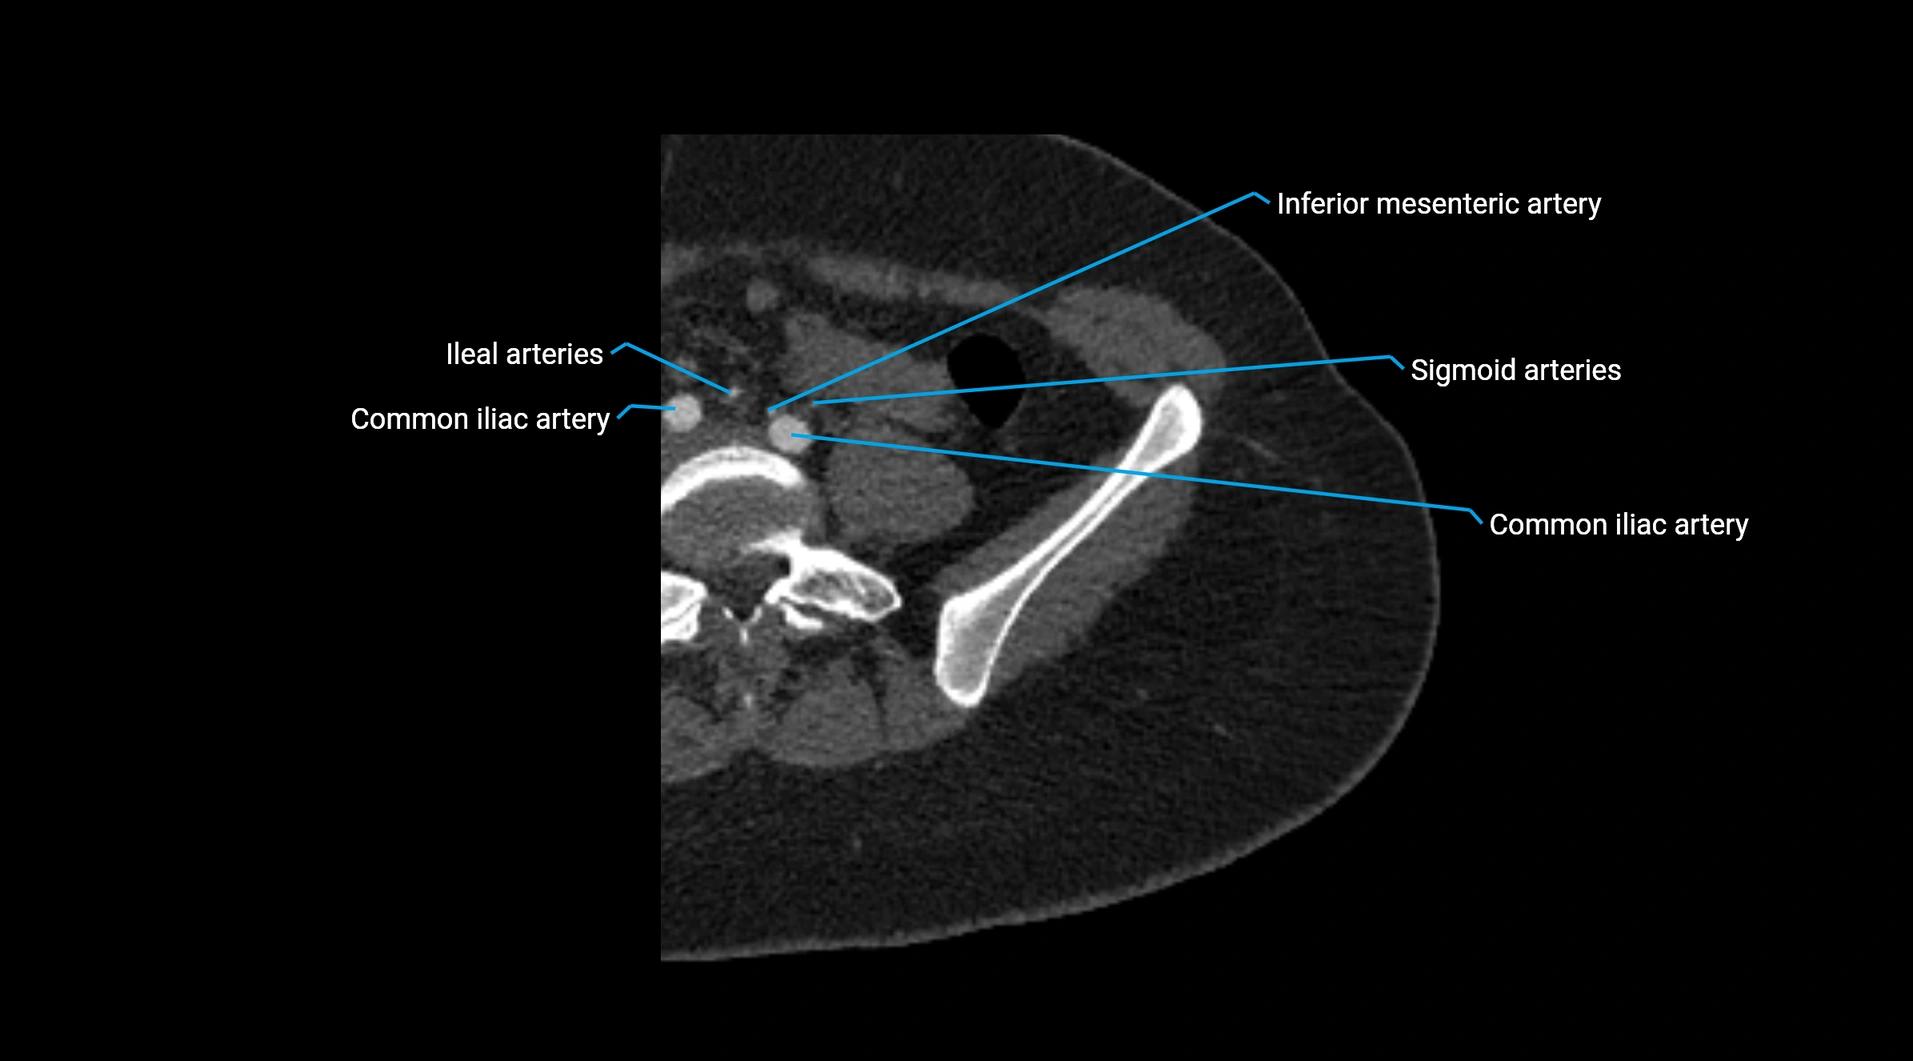

Branches

• Unpaired visceral branches: celiac trunk, superior mesenteric artery (SMA), inferior mesenteric artery (IMA)

• Paired visceral branches: middle suprarenal arteries, renal arteries, gonadal arteries (testicular or ovarian)

• Parietal branches: inferior phrenic arteries, lumbar arteries, median sacral artery

• Terminal branches: right and left common iliac arteries

CT Appearance

Contrast-enhanced CT (CTA):

• Gold standard for abdominal aortic imaging

• Provides excellent detail of lumen, wall, aneurysm, thrombus, and branch vessels

• Multiplanar and 3D reconstructions help in aneurysm measurement, stent graft planning, and dissection evaluation

• Detects acute rupture, traumatic injury, or occlusion with high sensitivity